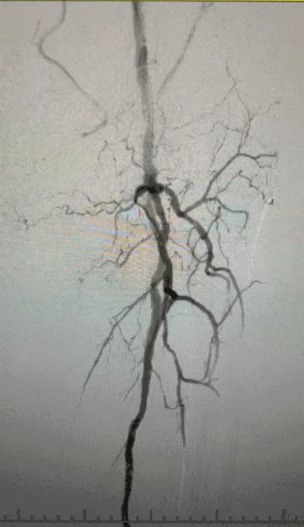

· Körperliche Untersuchung: Schwache Femur impulse; fehlende Popliteal-und Dorsalis-Pedis-Impulse; Geschwür am linken ersten Zeh; Nekrose am rechten ersten und zweiten Zehen

· Präoperative Bildgebung: Schwere, diffuse verkalkte Stenose in bilateralen Arterien der unteren Extremitäten

Angesichts des komplexen Gefäß zustands haben wir das ThorCrack Periphere IVL-Ballon dilatation katheters ystem ausgewählt. Aufgrund der begrenzten Toleranz des Patienten wurden inszenierte intervention elle Eingriffe an beiden unteren Gliedmaßen durchgeführt.

Chirurgisches Ergebnis